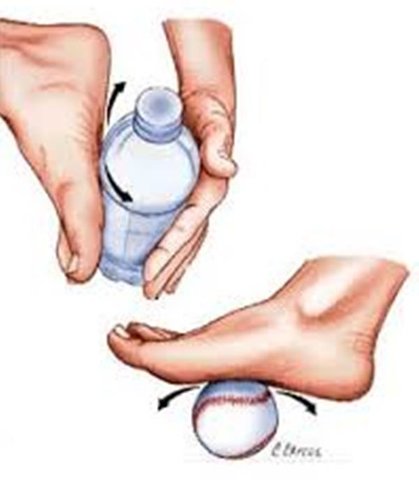

-استفاده از یخ (به مدت 20 دقیقه کف پا و منطقه پاشنه ماساژ داده شود)

2- شئی استوانه ای یا گرد مانند بطری یا توپ تنیس را روی زمین قرار داده و پا را روی آن بغلطانید. می توان برای ایجاد مقاومت بجای زمین از دستها کمک گرفت.